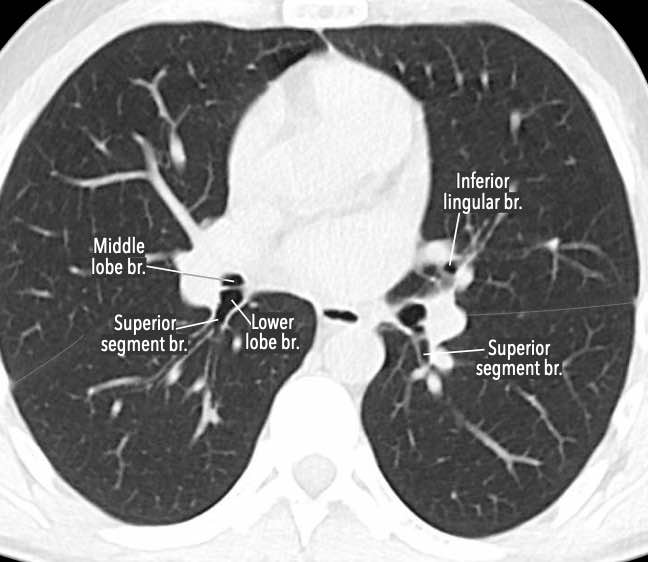

Phế quản trên CT

Cuộn qua các hình ảnh để quan sát khí quản phân chia thành phế quản chính phải và trái, sau đó tiếp tục phân chia thành các phế quản thùy và phế quản phân thùy.